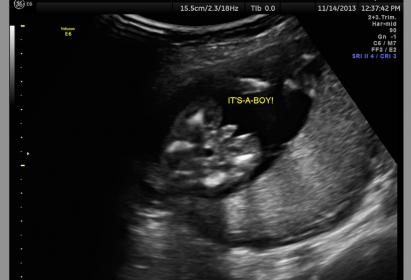

I'm only 15w4d...any chance this BOY is not a boy?

We were hoping girl....I agree that this looks pretty definitive, but I'm wondering if there's any chance that this is "swollen girl parts" or something.

Nope that is definitely a boy. You can see the attached scrotum in the second pic. I'm sorry you didn't get your dg though.